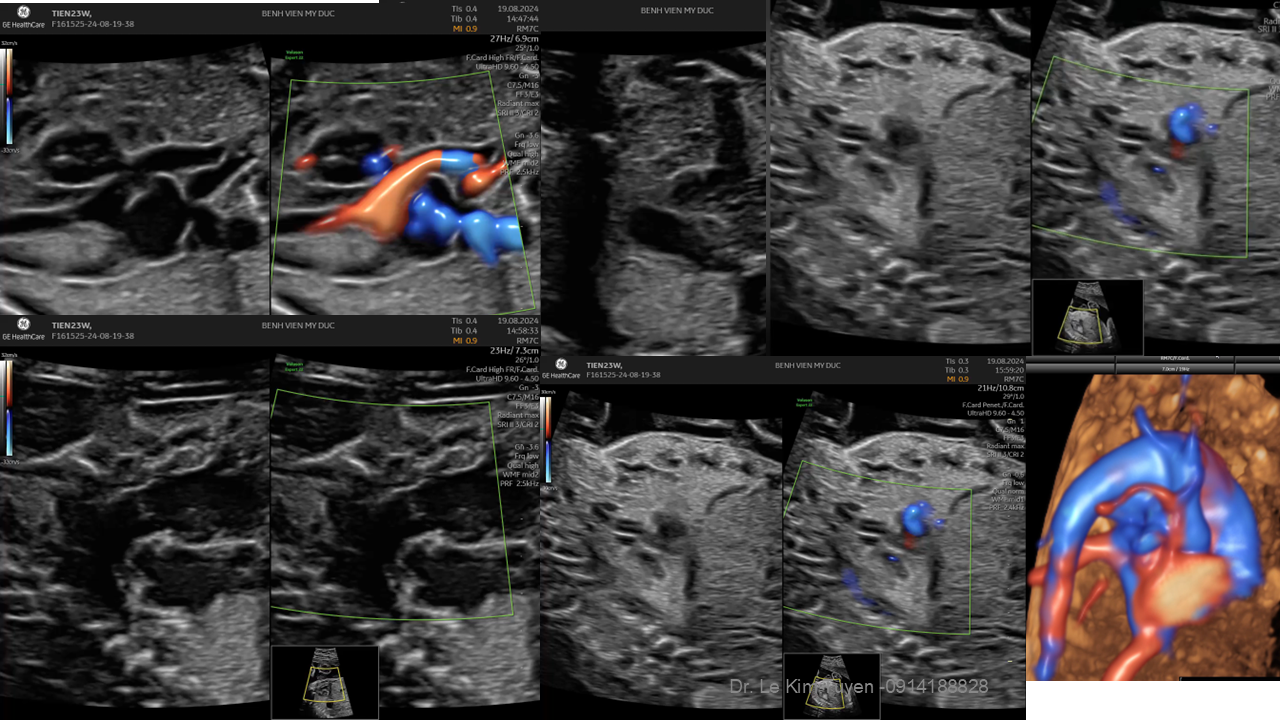

Áp dụng công nghệ Graphicflow trong phát hiện bệnh tim bẩm sinh cần cấp cứu sơ sinh

TS. BS. Lê Kim Tuyến